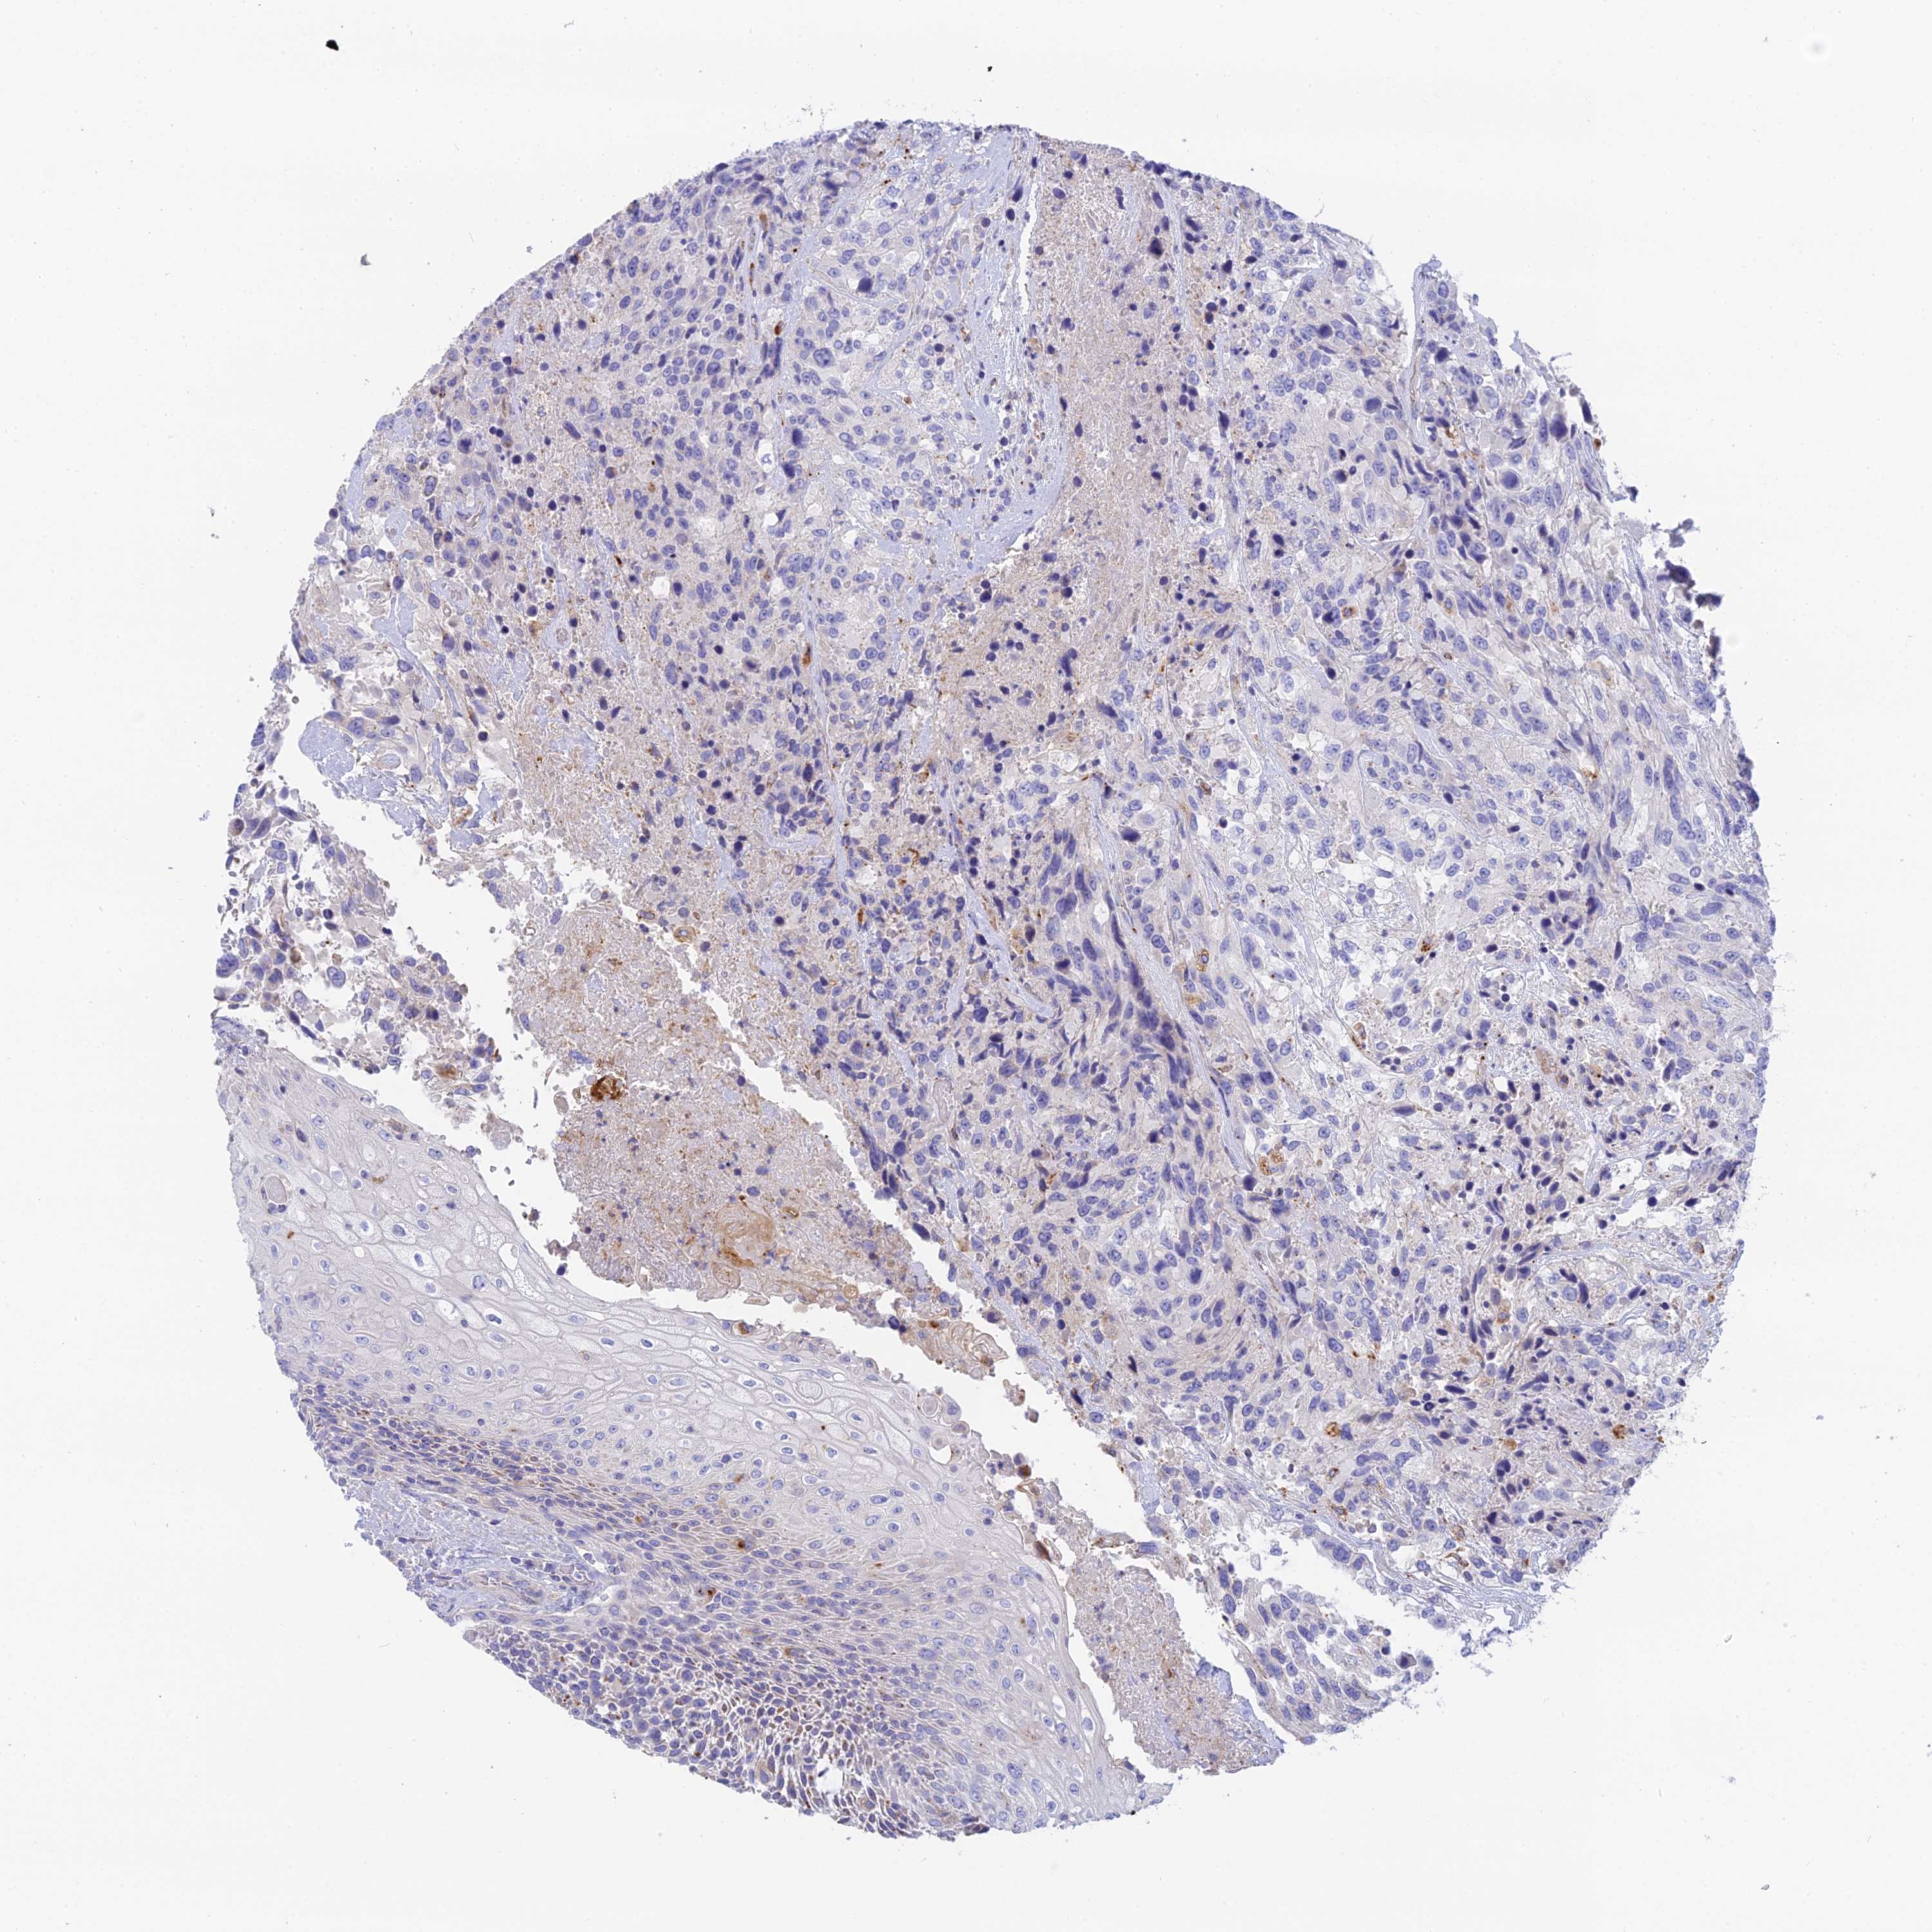

UROTHELIAL CANCER - Protein expressioni

A mouse-over function shows sample information and annotation data. Click on an image to view it in a full screen mode. Samples can be filtered based on level of antibody staining by selecting one or several of the following categories: high, medium, low and not detected. The assay and annotation is described here.

Note that samples used for immunohistochemistry by the Human Protein Atlas do not correspond to samples in the TCGA dataset.

Antibody stainingi

Antibody staining in the annotated cell types in the current human tissue is reported as not detected, low, medium, or high, based on conventional immunohistochemistry profiling in selected tissues. This score is based on the combination of the staining intensity and fraction of stained cells.

Each image is clickable and will lead to virtual microscopy that enables deeper exploration of all samples and also displays staining intensity scores, fraction scores and subcellular localization as well as patient and tissue information for each sample.

Antibody HPA042622

Staining

High

Medium

Low

Not detected

Intensity

Strong

Moderate

Weak

Negative

Quantity

>75%

75%-25%

<25%

None

Location

Nuclear

Cytoplasmic/membranous

Cytoplasmic/membranous,nuclear

Urothelial carcinoma, High grade

Urothelial carcinoma, Low grade